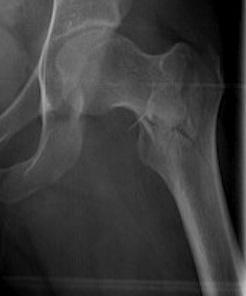

Isolated GT Fracture

Indications

- reverse oblique

- unstable fracture / loss of lateral buttress / loss posteromedial support

- subtrochanteric extension